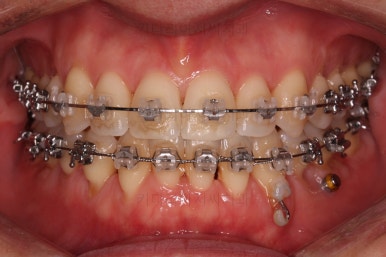

부산비수술교정 키다리아저씨치과에 처음 내원하셨을 당시의 입 안의 모습입니다.

아래 앞니에 결손치아가 하나 있네요. 송곳니-송곳니 사이에 앞니가 4개가 있어야 정상이지만 이 분은 3개에요. 의외로 아래앞니 하나 혹은 두개가 없는 경우가 굉장히 많답니다.

갯수가 맞지 않다보니 치열의 중앙도 맞지 않고 비대칭이 됩니다.

그리고 주걱턱이기 때문에 당연히 아랫니들도 앞으로 나올 수 밖에 없어 윗니보다 앞에 나와있어요.

이를 반대교합이라고 합니다.

어금니의 맞물림도 연쇄적으로 몇 칸씩 밀려있는 양상이라 효율도 좋지 못하고 치아의 건강에도 좋지 못해요.

이 분의 경우에도 전반적으로 잇몸이 약해져있을 수 밖에 없어요. 보시면 아시겠지만 잇몸 퇴축이 심해서 치아들이 길쭉길쭉해 보이죠.

장치를 처음 부착했을 때의 입안 모습입니다.

아랫니가 해야될 작업이 많고 기간이 오래 걸리기 때문에 윗니는 최대한 늦게 장치를 부착하여 불편감을 최소화 하기로 했어요.

이번에 사용한 장치는 자가결찰 세라믹장치입니다. Empower clear(엠파워 클리어)라는 장치이고 흔히 많이들 알고계신 클리피씨와 동일한 유형의 장치에요.